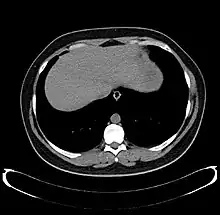

CT scan showing an adult liver in the axial plane.

Organogenesis, the development of the organs, takes place from the third to the eighth week during embryogenesis. The origins of the liver lie in both the ventral portion of the foregut endoderm (endoderm being one of the three embryonic germ layers) and the constituents of the adjacent septum transversum mesenchyme. In the human embryo, the hepatic diverticulum is the tube of endoderm that extends out from the foregut into the surrounding mesenchyme. The mesenchyme of septum transversum induces this endoderm to proliferate, to branch, and to form the glandular epithelium of the liver. A portion of the hepatic diverticulum (that region closest to the digestive tube) continues to function as the drainage duct of the liver, and a branch from this duct produces the gallbladder.[35] Besides signals from the septum transversum mesenchyme, fibroblast growth factor from the developing heart also contributes to hepatic competence, along with retinoic acid emanating from the lateral plate mesoderm. The hepatic endodermal cells undergo a morphological transition from columnar to pseudostratified resulting in thickening into the early liver bud. Their expansion forms a population of the bipotential hepatoblasts.[36] Hepatic stellate cells are derived from mesenchyme.[37]